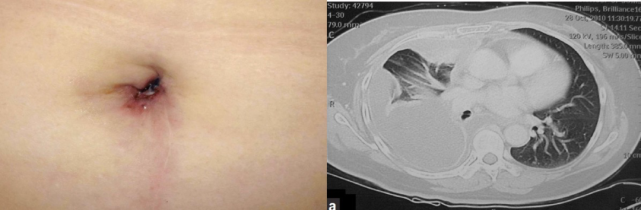

图片

一位有 Sister Mary Joseph’s nodule 的 51 岁女性,CT 示右侧胸腔积液、右肺不张及肺实质高密度影,病理证实为肺腺癌(图片来自文献 [15])